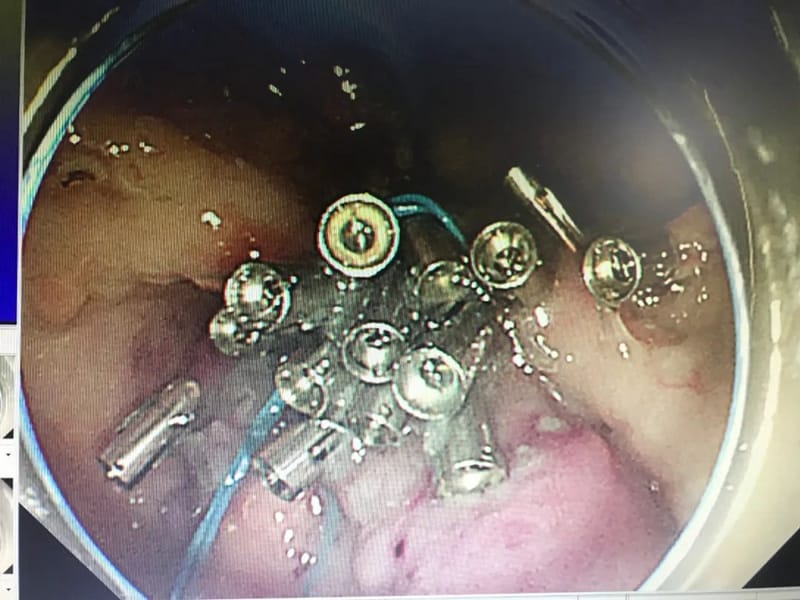

89岁高龄的男性患者张某,因外院结肠镜检查发现一枚大小约1.8*1.5cm的直肠侧向发育型肿瘤入院,原本这么高龄的患者,常规采用保守治疗,经郭军主任查看病人,考虑其直肠侧向发育型肿瘤为早期病变,全麻插管下内镜下微创切除无疑是最好的选择,且老人身体健康,无基础性疾病,手术指征良好,在充分的讨论后,建议内镜下微创切除。在经得患者及家属同意后,消化内科团队与麻醉与围术期医学科医师密切配合,成功为患者实施了经内镜直肠病灶粘膜剥离术,病灶完整切除,手术顺利,术后患者恢复良好。

13岁患儿薛某某,是一名黑斑息肉综合征的患者,有结肠癌家族史,因消化道出血入院,在完善胃肠镜检查发现其以胃内为主有几十枚息肉样病变,其中最大者达到6*6.5cm,为了让患儿能得到最合理、最优化、最小创伤的治疗,郭军主任团队进行了多次术前讨论。最终确定胃镜、肠镜下经内镜息肉切除,但行内镜切除的话,手术难度大,风险高。在充分术前准备后,郭军主任经过3小时的内镜下手术,患儿病灶被完整切除,现恢复良好,进入密切随访阶段。